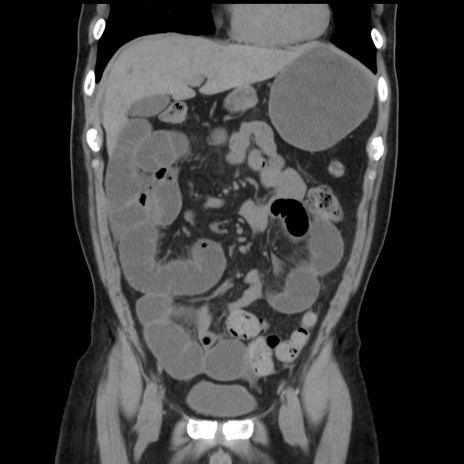

症例16(冠状断像)

【症例】 70歳代男性

【主訴】 腹痛、嘔吐

【現病歴】 約1ヶ月前より間欠的に腹痛と嘔吐あり、当院消化器内科を受診したところCTで多発する肝臓のLDAを指摘され、精査中であった。以降は消化器症状は安定していたが、2日前より嘔気と腹痛があり、同日より排便・排ガスが消失した。改善認めず、 本日、救急外来を受診した。

【既往歴】 大腸ポリープ切除後。

【身体所見】意識清明・会話良好、BT 36.3℃、BP 127/80mmHg、 P 80bpm、腹部:膨満あり、平坦・軟、上腹部正中および下腹部正中に圧痛あり、反跳痛なし、筋性防御なし。

【データ】WBC 7200、CRP 0.77